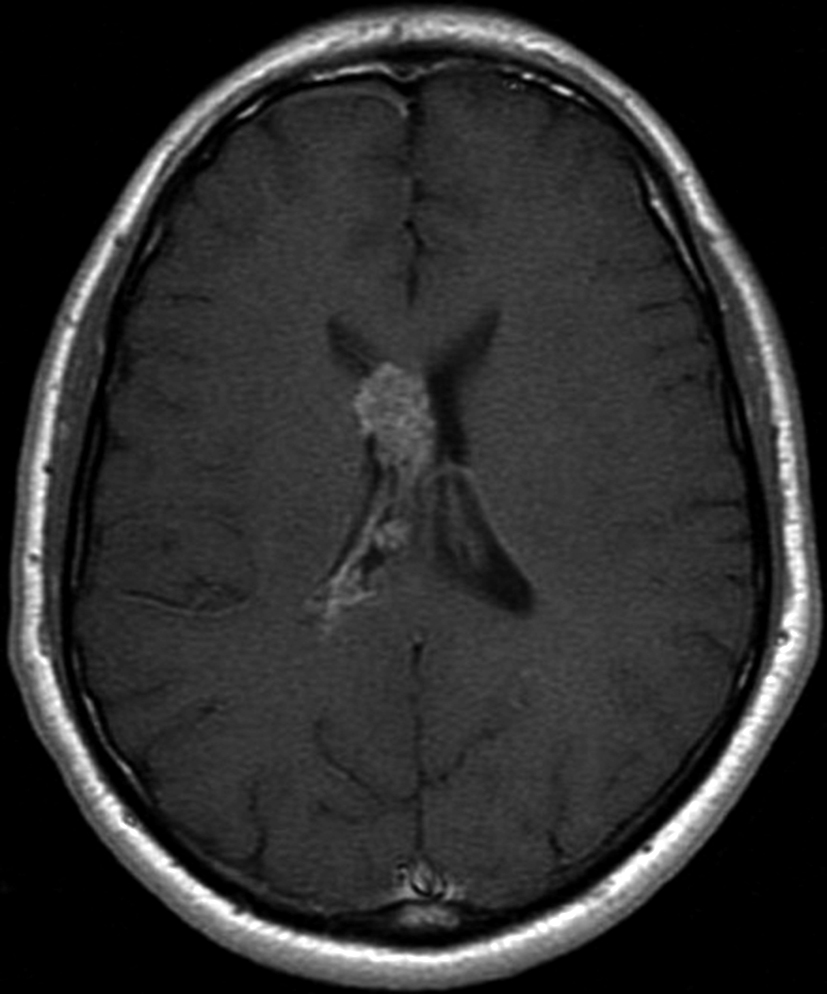

Figura 2 Resonancia magnética.

a) Imagen axial T1, lesión intraventricular con intensidad de señal heterogénea.

b) Tras la administración de Gadolinio no presenta realce significativo.

c) Imagen axial en secuencia ecogradiente donde se evidencia la lesión hipointensa y heterogénea. Se observa la extensión de la lesión al cuerpo calloso.

Con los hallazgos tomográficos, no se efectúan planteos diagnósticos y se realiza una resonancia magnética con la finalidad de obtener más datos semiológicos en busca de una aproximación diagnóstica. Se realizó el estudio por medio de secuencias T 1, FSE T 2, FLAIR, SWI y Difusión, en cortes axiales, FSE coronal y sagital T 1. Se realiza la administración de gadolinio DTPA en los tres planos. Se evidencia la lesión bien definida a nivel del ventrículo lateral derecho, que involucra al tronco del cuerpo calloso (Figura 2- C y 3- B). Presenta intensidad de señal heterogénea en secuencias T1 y T2 (Figura 3 y Figura 4). En secuencia ecogradiente se observa una señal marcadamente hipointensa y heterogénea, con un halo hipointenso bien definido (Figura 2- C). No presenta realce significativo tras la administración de Gadolinio (Figura 2- B) y en la secuencia de difusión no presenta restricción.